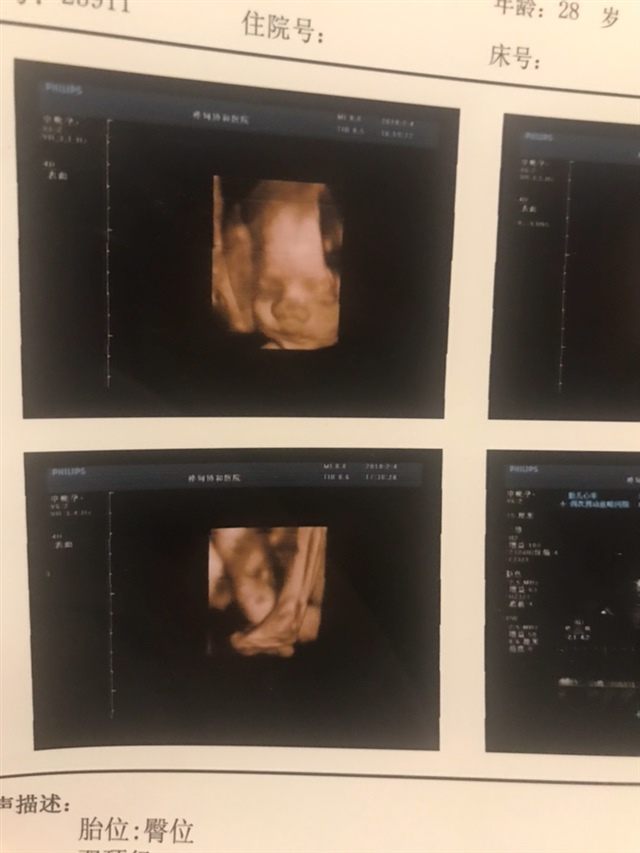

看到脸了,好可爱哈哈